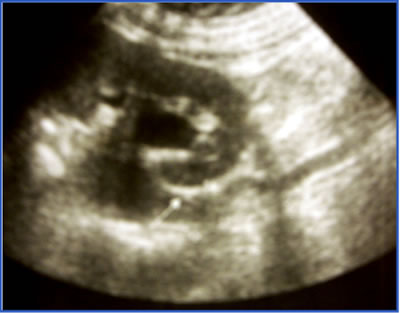

|

УЗИ

левой почки |

при остеосцинтиграфии и УЗИ печени: данных за

метастазы не получено.

при динамической нефросцинтиграфии

– секреторно-эвакуаторная функция обеих почек

в пределах нормы |